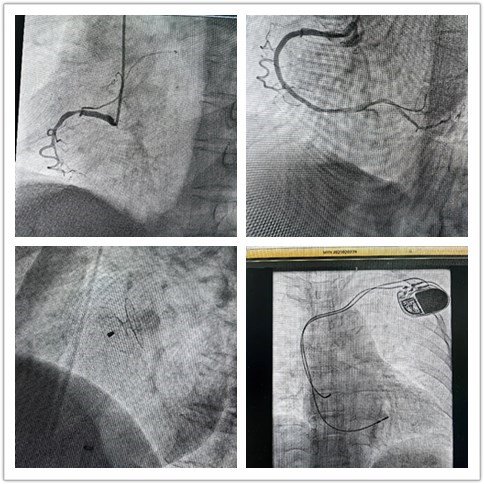

,血压低、精神状态差,已进入心源性休克状态,随时可能失去生命。长期驻扎的黑料网“组团式”帮扶队员—心内科邓纪钊,立即组织指导多学科团队开通胸痛绿色通道,有条不紊进行急诊术前相关检查,诊断为急性下壁心肌梗死。绕行病房,直达介入手术室,仅用32分钟顺利开通血管,患者转危为安,预后良好。

心内科救治能力和水平不断提高,业务范围不断扩展,先后完成多例卵圆孔未闭封堵、永久性心脏起搏器植入、心律失常射频消融术等。县黑料网

从2022年3月组建介入科至今,截至发稿,冠脉介入手术已逾1000例,急诊冠脉内介入治疗手术已过百例,无1例手术相关医疗事件发生。这是镇安县黑料网